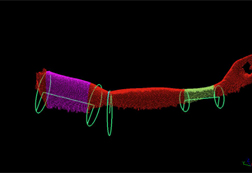

使い勝手が改善された測定用ターゲット

スキャニングのワークフローではデータの位置合わせに、ターゲットや球体ターゲットなどを使用します。その際 Artec Studio 17なら、より簡単に位置合わせを実行できます。作業中のワークスペース内でオブジェクトを確認し、ターゲットを位置合わせの基準点として選択します。ターゲット間の距離を測定したり、位置ずれや欠損の生じている箇所を特定し、位置合わせから除外できます。また、参照用ターゲットクラウドをワークスペースにインポートして、その中からトラッキングに使用するものを選択できます。

1. 従来のマニュアル測定方法に代え、非接触ハンディ3Dスキャナーで関節の曲がり状態を調べる。